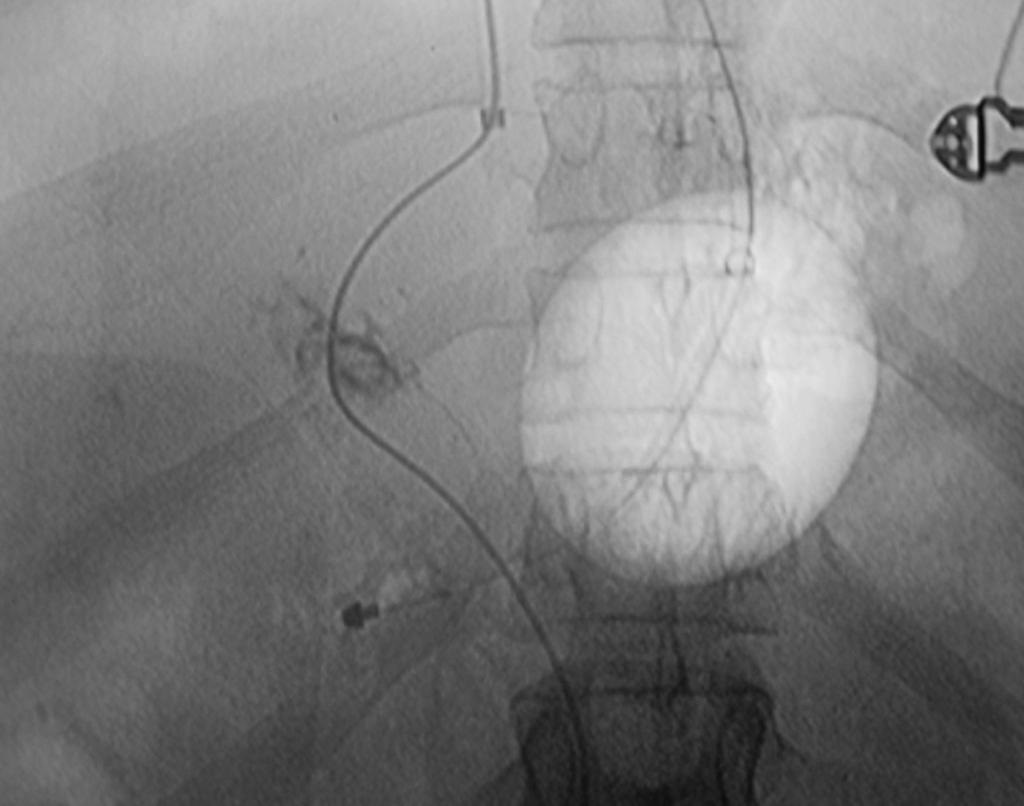

病例2:经左肝静脉-左门静脉穿刺,支撑架植入术

肠系膜上静脉血栓TIPS